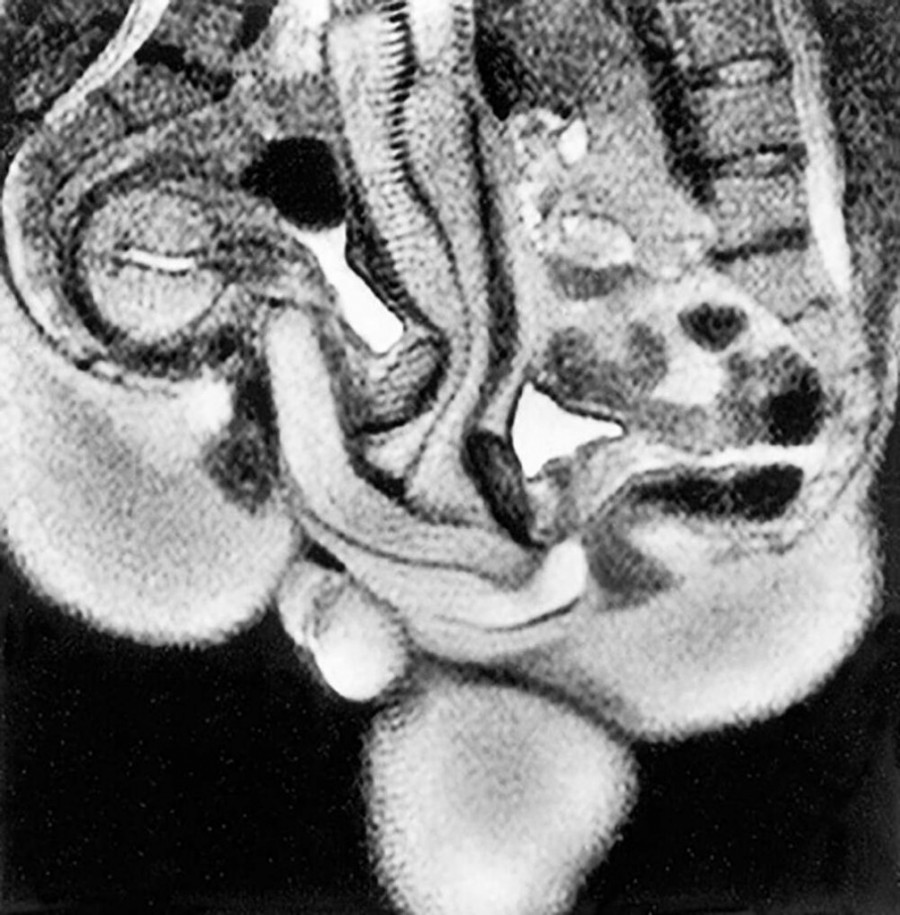

Dugo je vladalo verovanje da muški penis ide ravno u vaginu i izlazi na isti način. Time se vodio i slikar Leonardo da Vinči koji je nekoliko vekova ranije, tačnije 1492. godine, na svojim crtežima vaginu prikazao kao pravi cilindar.

No, magnetna rezonanca pokazala je da “penis ima oblik bumeranga”, što znači da se savija prema obliku ženskog tela, a da muškarca ne boli tokom erekcije. Nakon Ide i Jupa, kasnije je sprovedeno još nekoliko eksperimenata intimnog odnosa u magnetnoj rezonanci. U pitanju su bili volonteri stariji od 18 godina koji su mogli odustati bilo kada. Kao što je Ida istakla tokom nedavnog intervjua, niko osim Jupe i nje nije mogao završiti test bez upotrebe viagre.